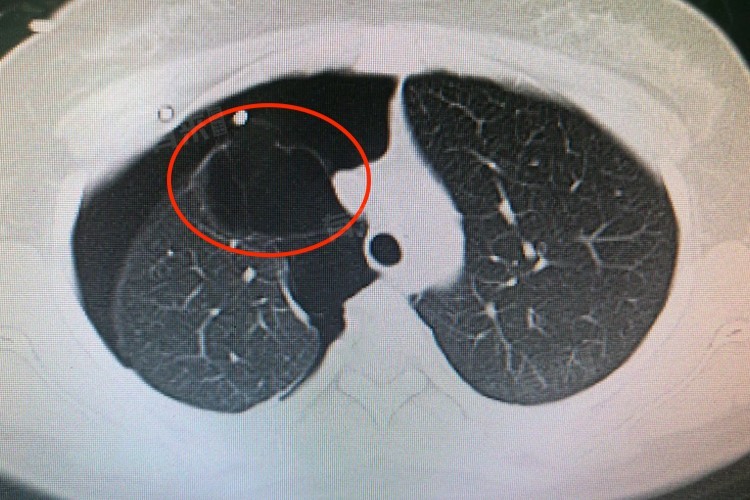

- 胸部X线检查是初步诊断的方法之一,可以看到肺部的透亮区域,提示可能存在肺大疱,胸部CT检查更加准确,能够清晰地显示肺大疱的大小、位置和数量,还能发现一些隐藏在肺组织深部的小肺大疱。